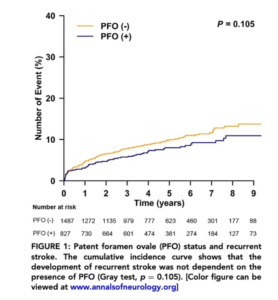

卵円孔開存が存在する脳梗塞は、卵円孔開存があるから再発しやすい訳ではないのは、皆さんの臨床実感の通りです。やはり、若くて「卵円孔開存が関与している可能性が高い(PASCALシステムで評価)」場合ほど、脳梗塞再発率は低いです。「PFOが関与していると断定できない症例は再発率が高い」、すなわち古典的な再発リスク因子が沢山あることの裏返しですね。

※詳細は以下の画像をクリックしてご覧ください。